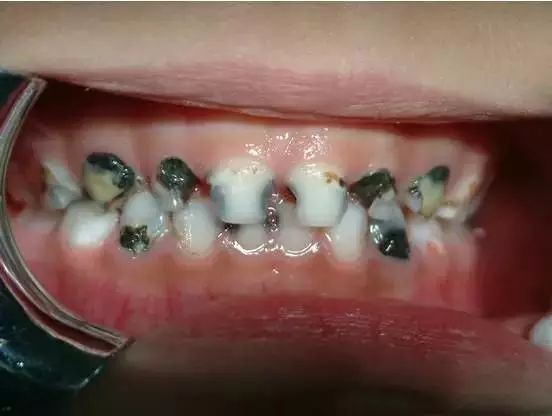

这是一个来自美国的真实案例。这位酷爱可乐的男孩年纪轻轻就失去了所有的牙齿不得不装上全口假牙。

在医学领域,这一现象被称作“酸蚀症”,简单来说就是牙齿长期广泛接触酸性物质造成的牙齿硬组织溶解丧失。

特别需要重点指出的是:对于儿童来说,饮料的杀伤力更大!因为刚萌出的牙齿尚未钙化完全,更容易被酸性物质溶解侵蚀。更何况,小朋友还特别喜欢喝甜甜的饮料,同时又尚未掌握刷牙的正确技巧。

所以在此提醒各位家长:让你的孩子尽量少喝饮料!